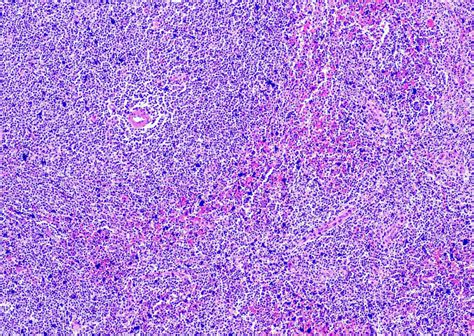

Mantle cell lymphoma (MCL) presents as a relatively uncommon, yet aggressive, non-Hodgkin lymphoma (NHL) that necessitates specialized hematological understanding. The disease, originating in the mantle zone of lymph nodes, involves the uncontrolled proliferation of B-cells, frequently leading to complex clinical presentations. Comprehending the nuances of MCL requires a deep dive into hematology, the branch of medicine concerned with the study of blood, blood-forming organs, and blood diseases.

Lymph node biopsies are the cornerstone of diagnosis, typically involving the removal of a portion or the entirety of an affected lymph node for microscopic examination. Immunohistochemical staining is essential for confirming the diagnosis and differentiating MCL from other lymphoma subtypes. As stated by an organization of hematologists, "Immunophenotyping, using flow cytometry, further characterizes the lymphoma cells based on their surface markers."